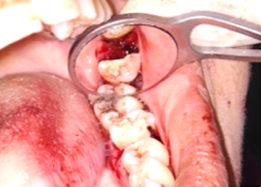

Half of Lower molar tooth along with diseased root removed & rest part is saved.

Post-OP Clinical View